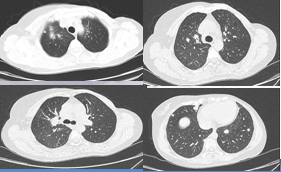

2018-10-26:患者出现咳嗽、咳痰,复查CT示:1.右肺上叶前段支气管狭窄、闭塞并周围、邻近右肺门软组织肿块形成,范围约3.2cm*2.7cm*2.6cm,病灶包绕右肺动脉,粘连上腔静脉,纵膈2R、4R、7组淋巴结肿大,考虑转移;2.双肺结节,部分融合,建议抗炎后复查;3.右侧肩背部、双侧下胸部皮下结节,转移待排。

2018年10月26号

2019-10-16:右肺病灶较前缩小,约1.4*1.0cm,双肺多发结节较前部分缩小,右肺上叶结节较前增多,纵膈肿大淋巴结较前略缩小,短径小于1cm,右肺炎变较前吸收,右侧肩背部皮下结节较前缩小。